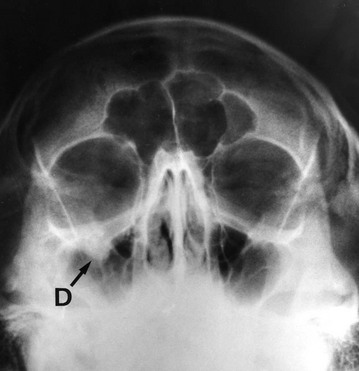

Fig. 16.11 Depressed zygomatic fractures

(a) Submento-vertical projection of a 43-year-old man who had been punched on the left cheek showing a depressed fracture of the zygomatic arch (arrowed). (b) 30° Occipito-mental radiograph after a similar injury in a different patient. This patient had a depressed ‘tripod’ fracture of the zygoma manifest by discontinuity of the lower orbital margin (arrowed). Note that since the roof of the maxilla is involved, the maxillary sinus (the antrum) has typically filled with blood and is rendered radiopaque. (c) 3D reconstruction of CT scans showing a severely depressed fracture of right lower orbital rim involving maxilla and zygomatic body (arrowed). The left lower orbital rim is also fractured and displaced